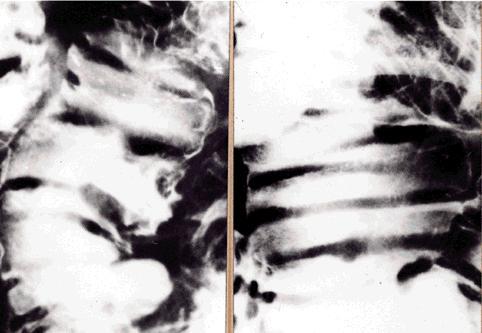

疾病(病理主体)的分类恶性淋巴系统・血液系统肿瘤/ATL (成人,ATL细胞白血病)

部位(按器官分)小肠/空肠

检查方法X线